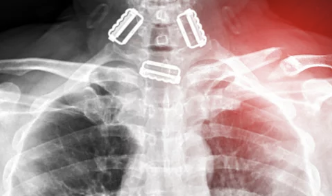

- 수술적 치료: 뼈가 여러 조각으로 부서졌거나 골절 상태가 복잡한 경우에는 금속판이나 나사로 뼈를 고정하는 수술적 치료가 필요해요. 수술적 치료는 빠른 회복을 기대할 수 있지만, 수술 후 합병증 가능성에 주의해야 해요.